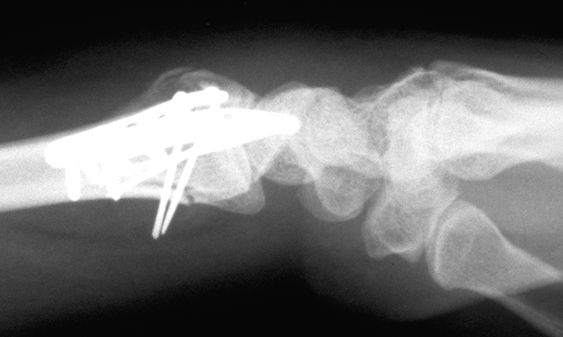

Case 1 Postop